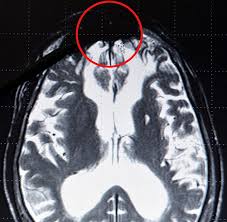

Ο Γερμανός νευρολόγος δρ Gerhard Roth, καθηγητής του Πανεπιστημίου της Βρέμης, υποστηρίζει  ότι μία σκοτεινή μάζα που βρίσκεται στο κέντρο  του εγκεφάλου αποτελεί δείκτη βίαιης συμπεριφοράς.

Η σκοτεινή μάζα βρέθηκε σε όλες τις απεικονιστικές εξετάσεις του εγκεφάλου ατόμων με εγκληματική προσωπικότητα.  Διαπιστώθηκε μάλιστα, πως δεν παρουσίασαν δραστηριότητα στις περιοχές του εγκεφάλου που συνδέονται με συναισθήματα λύπης και συμπόνιας,

O Terre Constantine, διευθυντής του Brain Research Foundation και πρώην διευθυντής του Jack Miller Center for Peripheral Neuropathy εκφράζει σκεπτικισμό για το πόρισμα της μελέτης αλλά συμφωνεί πως όγκοι στον εγκέφαλο και ανωμαλίες όπως ατροφία σε τμήμα του εγκεφάλου που προκαλείται από κάποια ασθένεια, επηρεάζουν τη συμπεριφορά, την προσωπικότητα και τον τρόπο που επικοινωνούμε.

German neurologist says he's found a 'dark patch'

BioEdge, a blog dedicated to bioethics news, translated Roth's German into English: “This is definitely the region of the brain where evil is formed and where it lurks.” πηγή http://www.dailymail.co.uk/sciencetech/article-2273857/Neurologist-discovers-dark-patch-inside-brains-killers-rapists.html